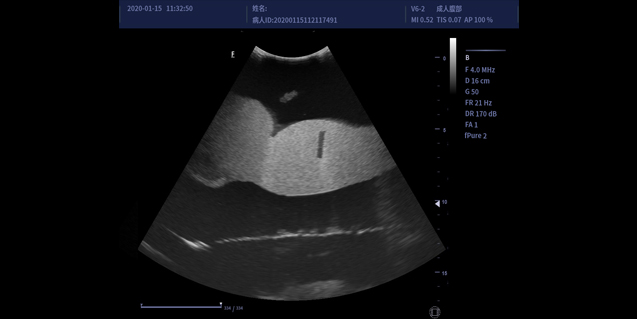

临床图像

凸阵探头C5-1

适用于腹部,妇产,泌尿等

容积探头V6-2

腹部,胎儿检查